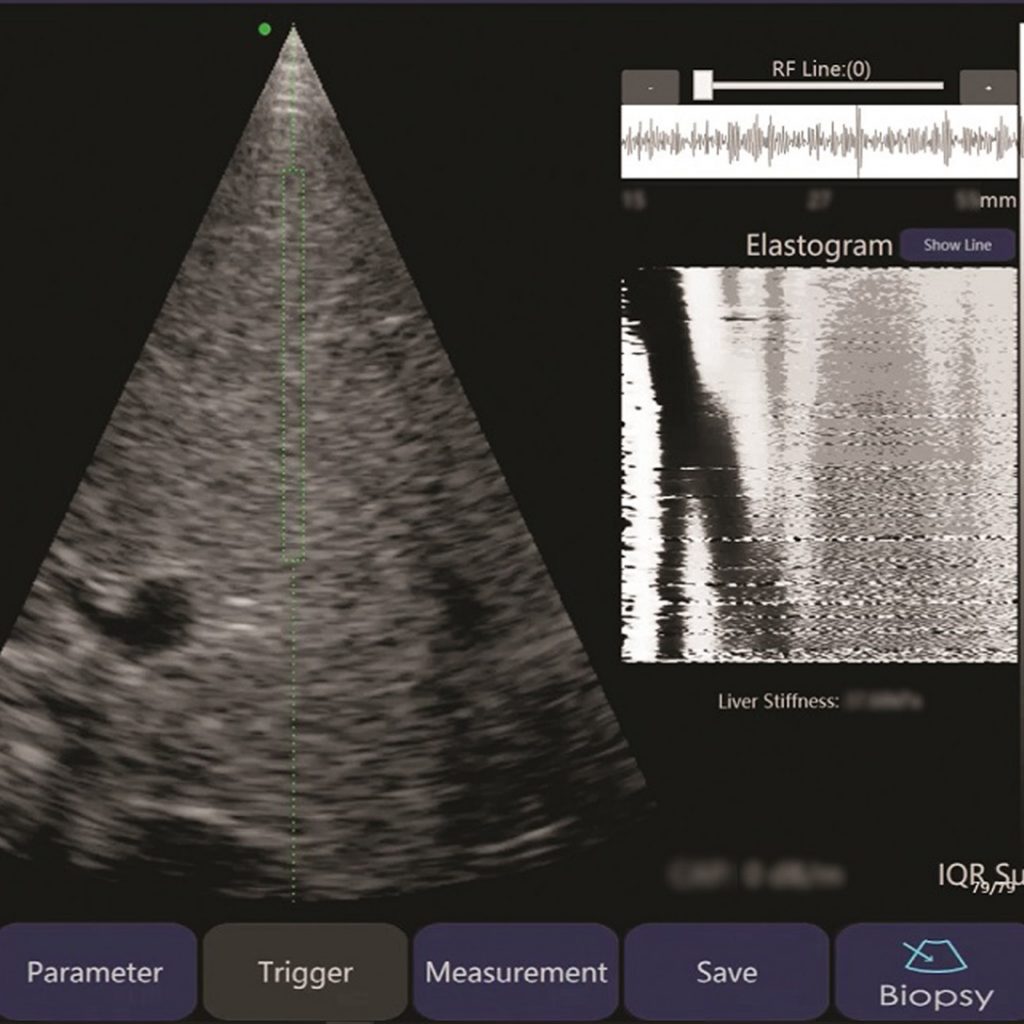

一部機點做?「掃一掃」背後係:超聲波數據+AI導引+即時質控

根據 PolyU 智齡研究院發布,FattaLab® 的工作流程以「一鍵式」為設計重心:

- 自動完成數據採集(data collection)

- 自動進行質量控制分析(quality control)

- 經流動端/App 即時輸出綜合報告

同一份資料亦提到:系統內置 AI會引導操作者辨識肝臟位置,令非專業人士都較易上手,並將 point-of-care 脂肪肝評估由「估算」推向「診斷級」取向(官方用語)。